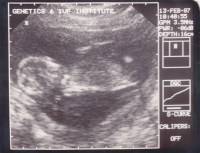

Alexandira at 12th and 13th weeks of gestation